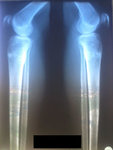

Рентген в 90 дней.